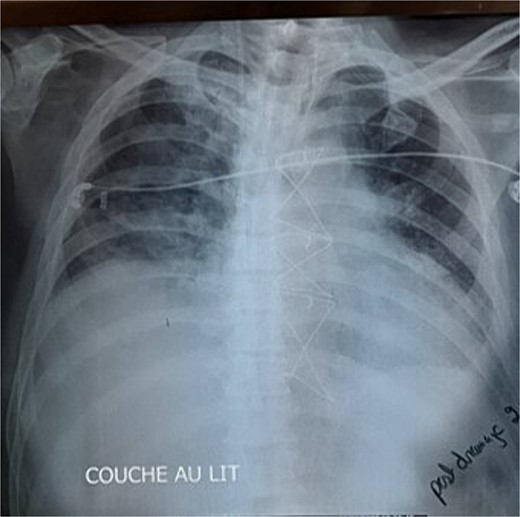

Given these findings, CABG was deemed necessary, with plans to place the left internal mammary artery (LIMA) to the LAD, right internal mammary artery (RIMA) to the RCA, and a saphenous vein graft to the first marginal. Intraoperatively, while dissecting the LIMA graft, total pericardial agenesis was unexpectedly discovered, manifesting as a collapsed parietal pleura and total leftward heart deviation. We performed uneventfully the CABG and we decided to not treat the pericardial agenesia. Postoperatively, the patient underwent extubating on the same day but developed non-sustained tachycardia on the electrocardiogram and recurrent unilateral pulmonary edema, particularly notable when he assumed a semi-upright position. The chest X-ray showed right pulmonary edema (Fig. 1), with total deviation of the heart to the left, as well as an elongation and straightening of the left heart border. The right cardiac border was also absent. The TTE showed an LVEF of 30%, high pulmonary arterial pressure = 50 mmHg. We hypothesized that this positional and unilateral pulmonary edema was related to the torsion of the heart and the elongated right pulmonary vein, caused by the deviation of the heart to the left due to the lack of pericardium.

The chest X-ray showed right pulmonary edema, with total deviation of the heart to the left, as well as an elongation and straightening of the left heart border.